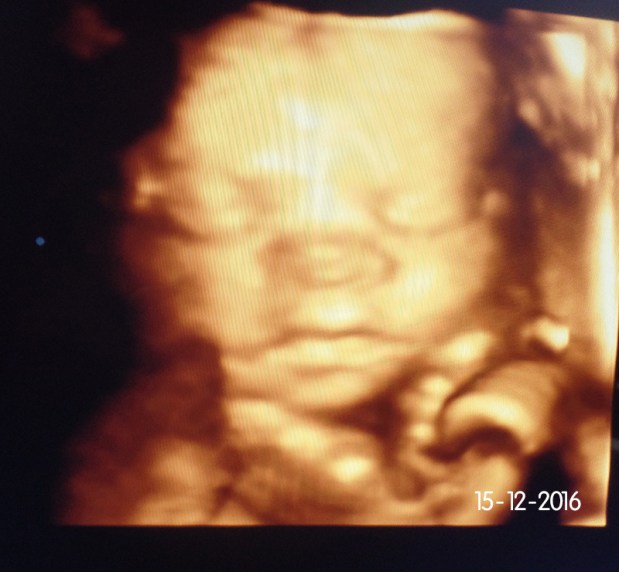

Ecografia 4D – a minha experiência

No dia 15 de Dezembro, dia do meu aniversário estava grávida de 29 semanas e decidimos que estava na hora de conhecermos a nossa bebé.

Não sei se sentem o mesmo mas por vezes parece que falta tanto tempo entre 1 ecografia e outra, principalmente à medida que o tempo passa e vamos ficando mais ansiosos para saber como será, que expressões fará e como está dentro da nossa barriga. Como presente de aniversário liguei para a Ecox e marquei uma ecografia 4D.

Todos os clientes da Ecologicalkids que compram packs de 12 ou mais fraldas reutilizáveis recebem um voucher de oferta de 5 minutos de ecografia 4D. Receei que pudesse não a ver e por isso decidi marcar para uma hora em que normalmente a nossa bebé está acordada. Vocês também já conseguem (ou conseguiam) saber os padrões de sono/atividade do vosso bebé? Caso não consigam ver a carinha nessa ecografia não se preocupem podem remarcar até conseguirem ver o vosso bebé, já que por vezes estão de costas ou com a mão à frente e não conseguimos ver com nitidez.

Ao contrário das ecografias que fazemos cujo objectivo é puramente médico nomeadamente avaliar as condições físicas do nosso bebé e fazer as medições próprias de cada trimestre, na Ecografia 4D o objectivo é mesmo desfrutar do nosso bebé e ter um pequeno vislumbre de como está dentro do nosso útero. Se já tínhamos achado impressionante a forma como se vê nas Ecografias do 1º e 2º trimestre ver a 3D é uma experiência espetacular e a qualidade de imagem é impressionante e faz-nos sentir ainda mais próximos daquele ser pequenino que trazemos cá dentro, parece que torna tudo mais real.

Fomos atendidos com muito carinho no centro e a sala é decorada de acordo com o sexo do nosso bebé, por isso no vídeo se vê a parede com uma luz rosa (pais de gémeos de sexos diferentes não se preocupem eles têm tudo planeado para o vosso caso). Uma outra vantagem é podermos levar a familia e/ou amigos próximos que normalmente não conseguem acompanhar-nos numa ecografia comum, e aí podemos viver este momento e partilhar com pessoas especiais. Como era dia de semana acabámos por ir apenas os dois e devo confessar que foi a minha melhor prenda de aniversário. Marcámos para as 29 semanas pois entre as 27 e as 30 podemos identificar perfeitamente as suas feições, como boceja ou sorri e também algumas semelhanças com os papás e também já começa a acumular gordurinha e a ficar mais redondinha, mas podem marcar antes disso.

A nossa bebé estava de frente e deu para perfeitamente vermos a sua carinha, claro que para nós é a mais linda do mundo! 😛 é incrível como se consegue ver detalhes, expressões faciais e movimentos. Não consigo esconder que ver a cara da nossa filha é um misto de sensações que vai das lágrimas de felicidade profunda, passa pela apreensão, alguma ansiedade e volta de novo à ternura e amor extremo.

Temos algumas fotos e vídeos que tirámos durante a sessão para podermos partilhar convosco para que tenham uma ideia de como é.

Incrível como se vê não é? Aqui está a nossa bebé! Não é a coisinha mais fofinha do Mundo?